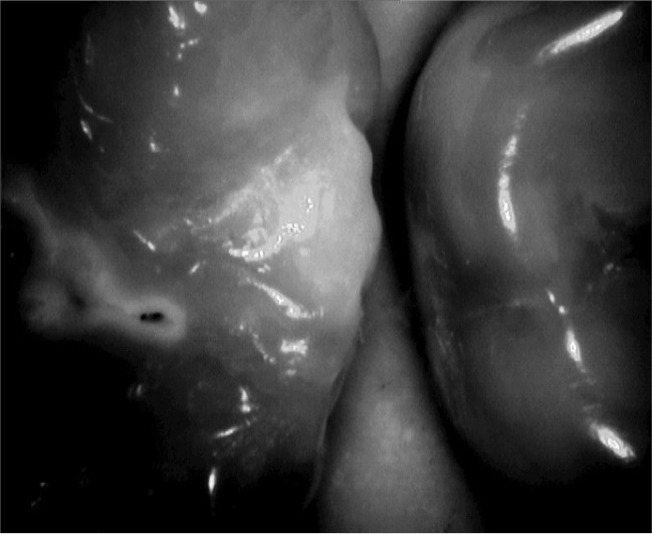

Materials and method: This in vitro study was performed on 40 extracted posterior teeth without cavitated carious lesions. Bitewing radiographs were obtained, infrared (IR) examination was performed, and the teeth were sectioned for histopathological analysis under a stereomicroscope as the gold standard for detection of caries and determination of the extent of carious lesions. Data were analyzed with Cohen's kappa statistic, and Wilcoxon rank sum test.